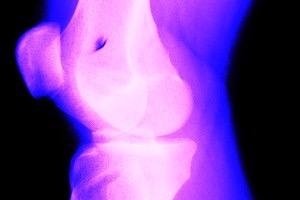

Crepitus can be caused by many things, and scientists are still not completely certain why it happens. One of the reasons for the popping sound may be that the patella is slightly out of alignment and is rubbing against the front of the femur or the adjacent soft tissue. Another condition called cavitation can cause a popping sound when small bubbles of carbon dioxide, which are normally suspended in the synovial fluid that lubricates the knee joint, form a larger bubble and make a popping sound as the knee is bent or twisted (think bubble wrap). Lax ligaments have been associated with an increase in cavitation. Changes in altitude or barometric pressure can often exacerbate the popping sound, such as on plane flights or when there is a change in the weather.

However, if the cracking or popping noise is accompanied by pain on a regular basis, or the knee catches or locks up, then you may have some cause for concern. Pain, sometimes accompanied by a grinding sensation, may be an indication that there is tissue damage to the articulating surfaces of the joint, such as tear to the meniscus. The cartilage behind the kneecap can fray, leading to the pain and popping sound of patellofemoral pain syndrome, which is generally caused by an overuse and misalignment of the hips, knees and ankles.